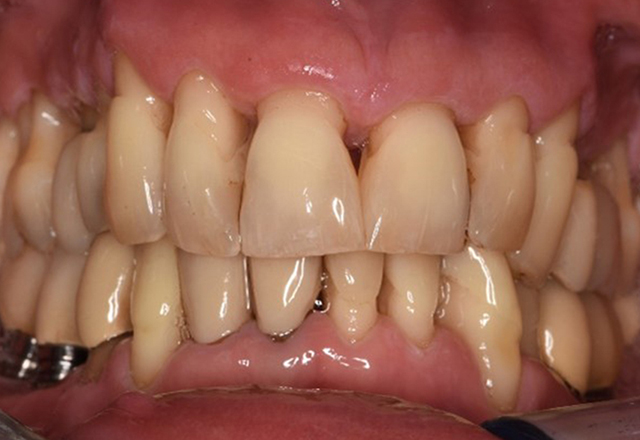

Un pacient în vârstă de 71 de ani, cu transplant de rinichi și istoric de hipertonie (hipertensiune arterială) se prezintă în cabinet. Din cauza istoricului său medical, este necesară o medicație pe termen lung cu ciclosporină, pentru a suprima sistemul imunitar, precum și amlodipină pentru a reduce tensiunea arterială. Pacientul raportează, de asemenea, gingii sensibile și sângerânde. Din punct de vedere al sănătății orale, pacientul are lucrări dentare, o edentație de opt dinți, creștere gingivală pronunțată și parodontoză de gradul B, stadiul II, cu pungi active și carii radiculare inițiale la dintele 22. Evaluarea riscului de carie determină un risc moderat de carie (API 60). Se pot stabili următoarele recomandări de tratament pentru ședința de profilaxie. mai multe